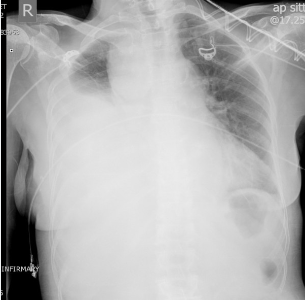

Quels sont les éléments permettant de soupçonner un hémothorax massif?

• Opacification unilatérale du poumon (zone blanche) à la radio pulmonaire